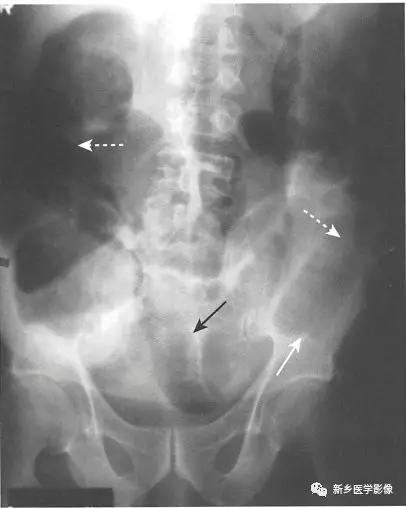

传统X线平片上,梗阻点近端可见多个扩张的小肠肠襻(>2.5cm)。

当肠 腔开始扩张,小肠肠襻逐一 堆积,形成阶梯状外观,一般由左上腹开始,随着疾病进展逐步向右下腹(黑色实线箭头)发展,具体范围及程度取决于小肠梗阻点有多远。

一般来说,若是近端小肠梗阻(例如近端空肠),则扩张的小肠肠襻数量较少;若是远端小肠梗阻(例如回盲瓣处),则扩张的小肠肠襻数量较多。

在直立位或侧卧位片上,在梗阻近端小肠通常可见多个气-液平面。

如果时间足够长,梗阻远端的肠道内容物可完全排出,则在结肠尤其是直肠内只有很少或完全见不到气体影。

在机械性小肠梗阻中,相对于塌陷的大肠,小肠往往表现为不成比例的显著扩张。